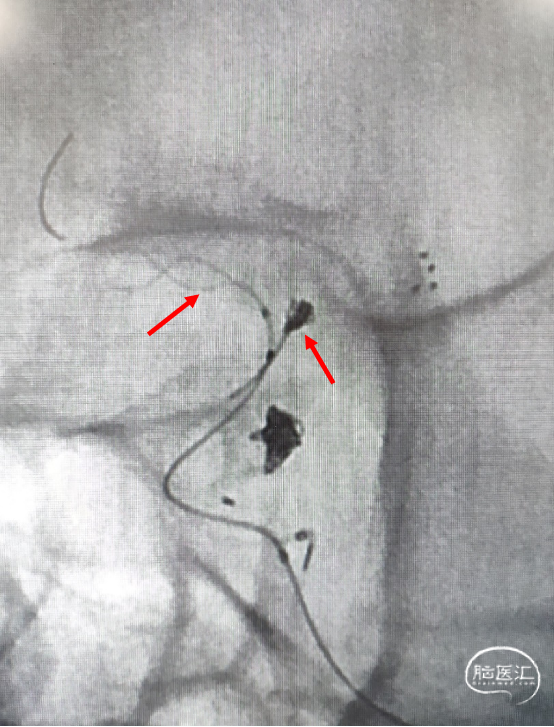

手术方案:穿网眼释放LEO+Baby支架与一期释放的支架形成T型,辅助弹簧圈栓塞。

2. 穿Solitaire支架网孔,将支架微导管及弹簧圈微导管分别超选到位。

3. 支架半释放后填圈。

支架微导管及弹簧圈微导管到位。

支架释放后,送入首枚2*4 2D的弹簧圈栓塞动脉瘤。

支架全释放。

支架全释放后送入第二枚1.5*2-2D弹簧圈。

术后造影显示动脉瘤致密栓塞,各分支血管血流通畅。

术后双容积成像显示支架头端完全覆盖动脉瘤瘤颈,并且与Solitaire支架形成“Kissing”,“T型”形成。